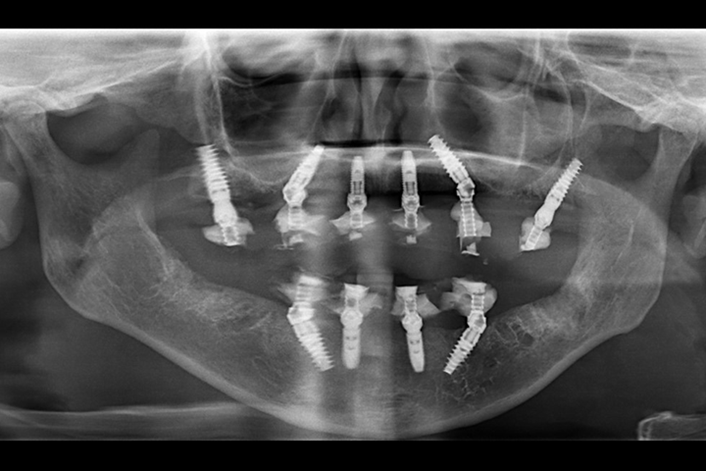

Now online in the Journal of Prosthodontics, Drs. Robert W. Slauch, Avinash S. Bidra, Glenn J. Wolfinger, and Chia-Ling Kuo examine if an uncorrected radiographically detected immediate postoperative misfit in immediately loaded conversion prosthesis plays a significant role in early implant or prosthesis failure. In addition, clinical characteristics were analyzed relative to their relationship to early implant or prosthesis failure.

The results showed that misfit in immediately loaded complete‐arch fixed implant‐supported prostheses may not play a detrimental role in the implant survival but may affect survival of the conversion prostheses.